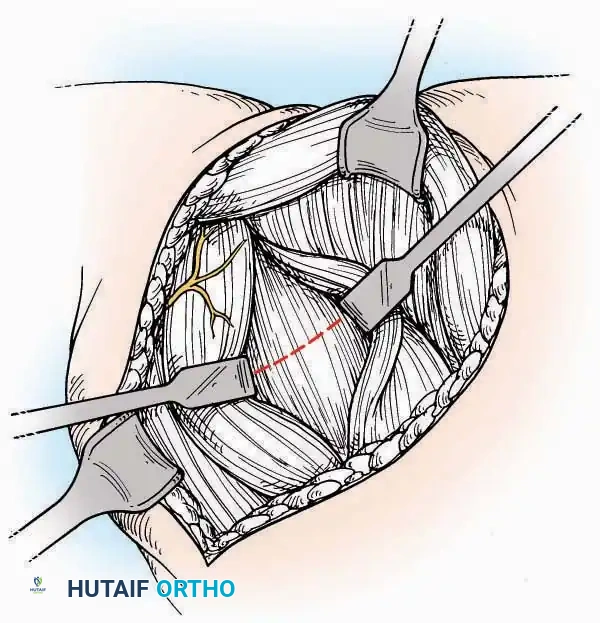

Surgical Technique:

* Incision: Begin the incision on the lateral margin of the Achilles tendon near its insertion. Extend it distally to a point 4 cm inferior and 2.5 cm anterior to the lateral malleolus. (For trauma, a classic L-shaped extensile incision is often used, dropping straight down anterior to the Achilles, then curving gently toward the base of the 5th metatarsal).

* Superficial Dissection: Divide the superficial and deep fasciae. It is imperative to create a "full-thickness" flap containing skin, subcutaneous fat, and periosteum to prevent flap necrosis.

* Nerve Protection: The sural nerve crosses the proximal and distal limbs of this approach. It must be identified and protected within the anterior flap.

* Deep Dissection: Isolate the peroneal tendons (longus and brevis). Incise and elevate the periosteum below the tendons to expose the lateral wall of the calcaneus.